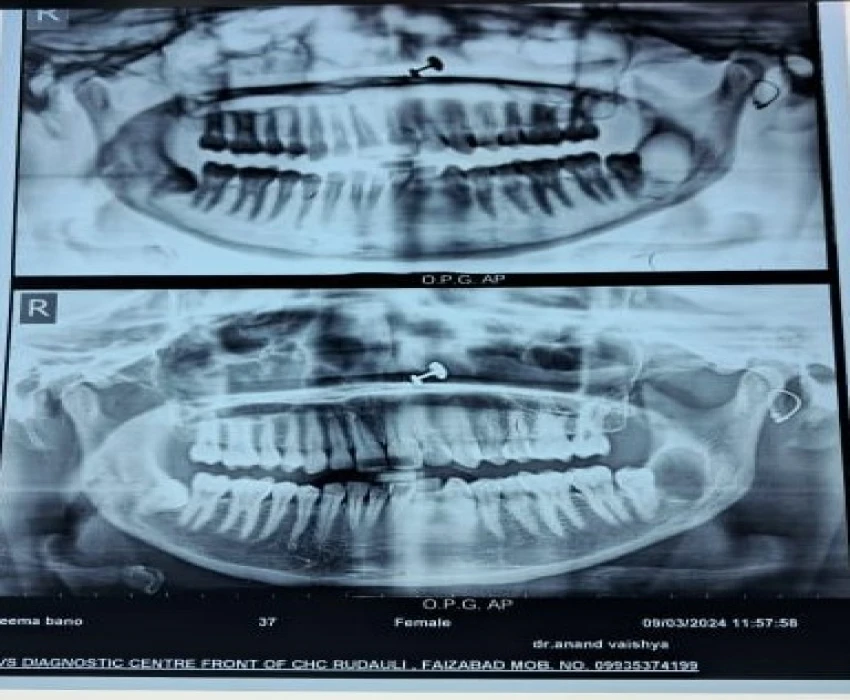

Based on radiographic findings provisional diagnosis was given as an infected cyst i.r.t 38.

The final diagnosis was given based on histopathological analysis as inflamed keratocyst i.r.t 38.